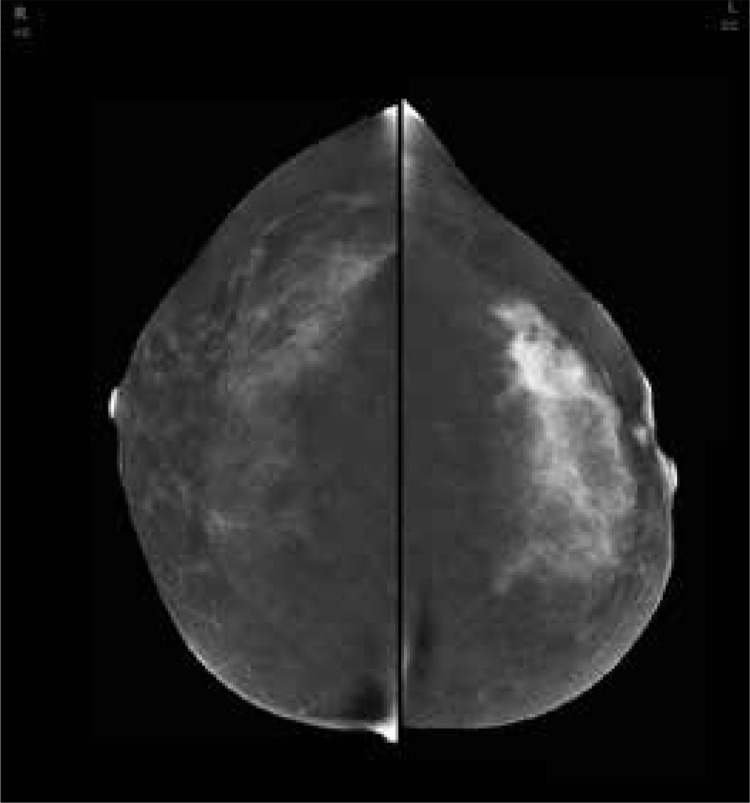

Purpose: This single-centre study includes a comparative analysis of the diagnostic performance of contrast-enhanced mammography (CEM) and automatic breast ultrasound (ABUS). The study involved 81 patients with focal breast lesions, who underwent ABUS, full-field digital mammography (FFDM), and CEM.

Material and methods: A total of 169 focal lesions were found in 81 patients, of which 110 lesions were histopathologically verified, 92 were malignant, 5 were B3 lesions, and 13 were benign. On CEM 19 additional lesions not visible on other imaging examinations were found, and as many as 36 new lesions were detected on ABUS. The number of lesions detected in patients with multiple lesions were 106 from 169 on ABUS, 65 on FFDM, and 88 on CEM. The highest correlation between the lesion's margin and its histopathological character was found in FFDM (p < 0.00), then ABUS (p = 0.038), and the lowest in CEM (p = 0.043). Compliance in determining the lesions' size comparing to histopathology as a gold standard was the highest for ABUS (p = 0.258) and lower for CEM (p = 0.012).

Results: The sensitivity of ABUS, FFDM, and CEM was, respectively: 80.43, 90.22, and 93.48; specificity: 27.78, 11.11, and 11.11; positive predictive value (PPV): 85.06, 83.84, and 84.31; negative predictive value (NPV): 21.74, 18.18, and 25; and accuracy: 71.82, 77.27, and 80. The sensitivity and accuracy of the combination of FFDM and ABUS were, respectively, 100 (p = 0.02) and 84.55 (AUC = 0.947) and for the combination of FFDM + CEM 93.48 (p = 0.25) and 79.09 (AUC = 0.855).

Conclusions: The study confirms that both ABUS and CEM may serve as a valuable complementary method for FFDM.